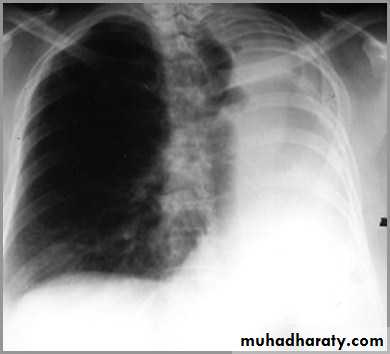

Differentiating the Causes of an Opacified Hemithorax

And a fourth cause: Post-pneumonectomy – removal of an entire lung

postpnemonectomy

The hemithorax eventually fibroses and becomes opaqueClues: There is frequently a resected fifth rib and/or surgical clips